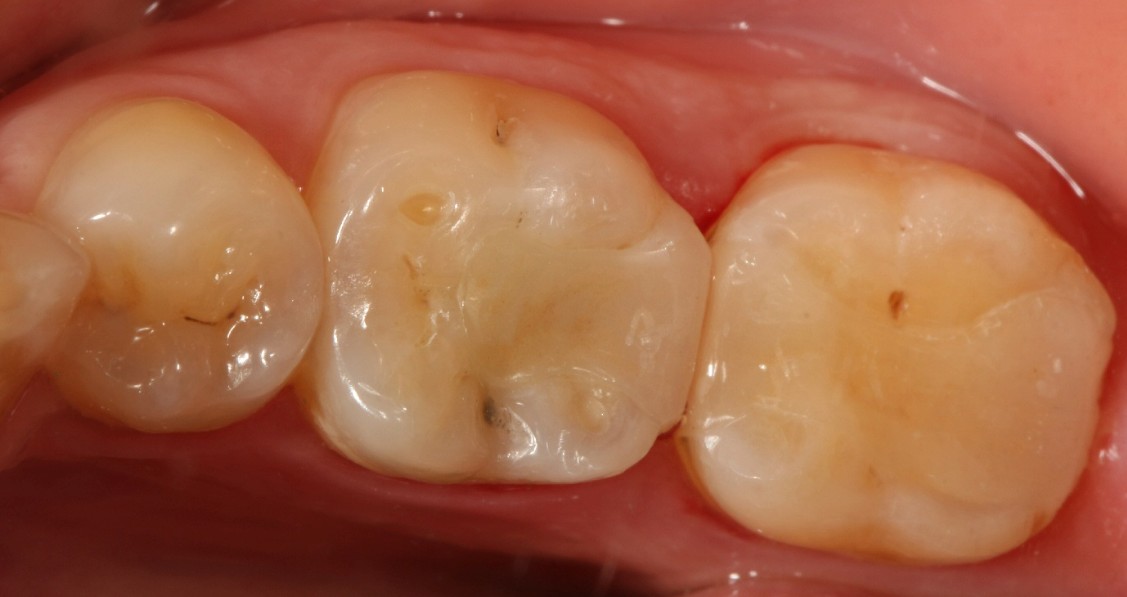

口腔检查时,会经常遇到以前补的银汞合金边缘变色,探有卡顿,形成了继发龋坏,建议重新充填或者瓷嵌体修复;瓷嵌体修复技术,可以非常好的恢复牙体形态和非常密合的边缘,色泽也非常逼真;我们采用CEREC(德国瓷睿刻)椅旁加工技术,达到最佳修复效果!